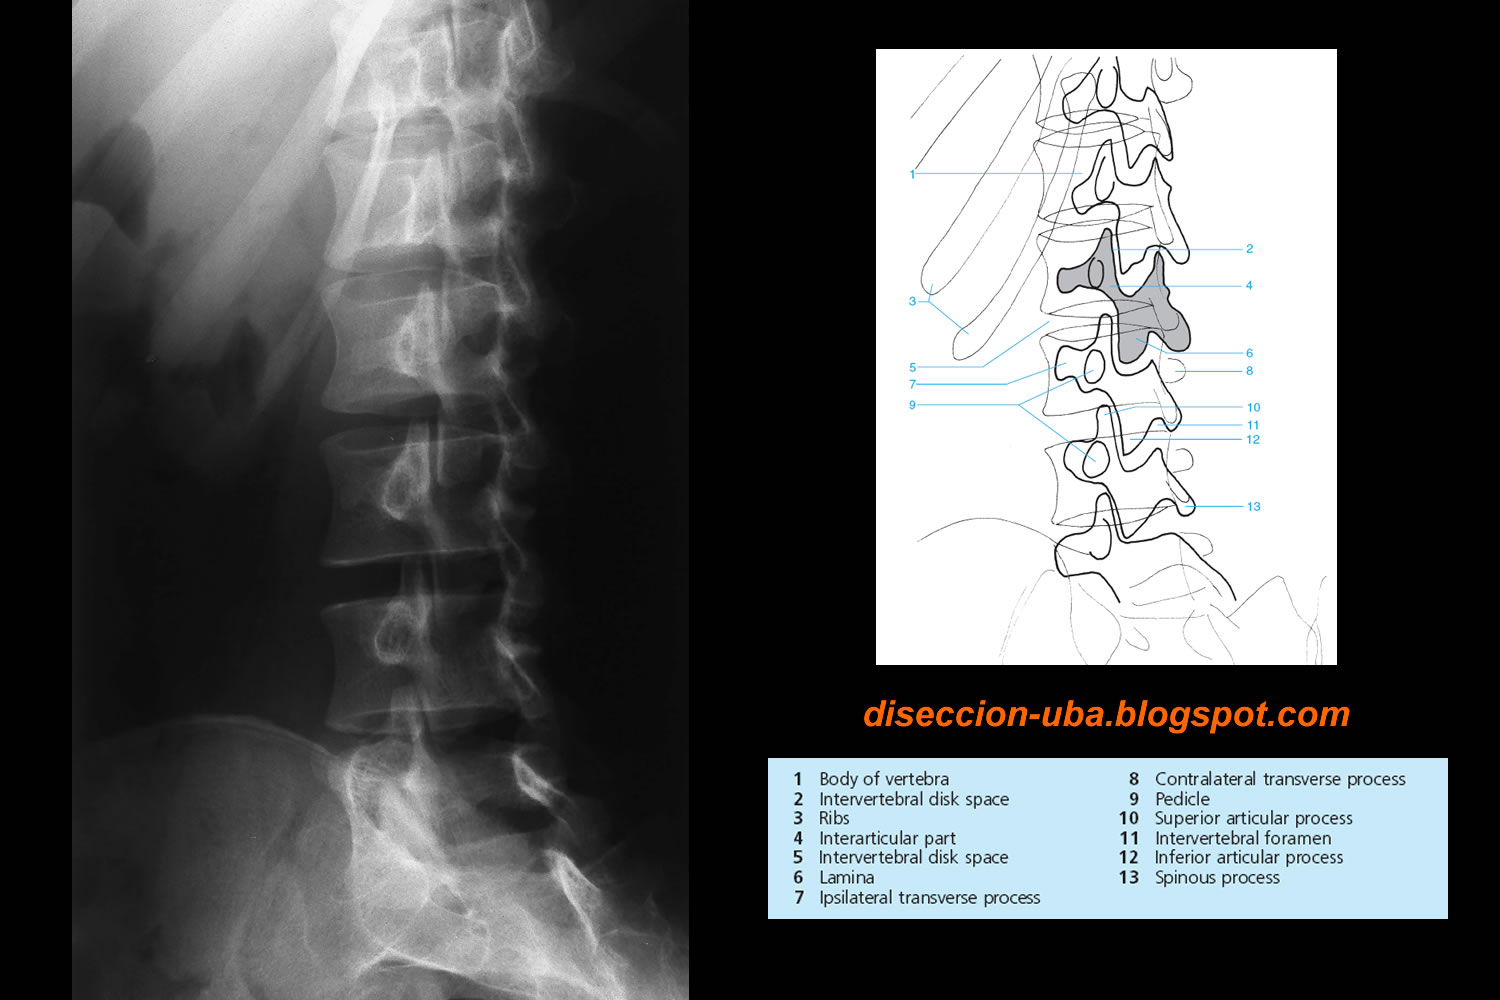

Rx Oblicua De Columna Lumbar

WebRadiografías de la columna vertebral. Este módulo de radioanatomía de la columna vertebral presenta 18 radiografías convencionales de la espina dorsal con. WebDescripción Se encarga de valorar la columna lumbar en seis posiciones distintas con el fin de encontrar cualquier tipo de lesión o problema en ella Requerimiento No requiere.

Web- Rx coumna cervical oblicua - Rx columna torácica anteropost. - Rx columna torácica lateral - Rx columna lumbar anteropost. - Rx columna lumbar lateral - Rx columna lumbar.

WebProyecciones oblicuas para los agujeros de conjunción (toda la columna) En la proyección oblicua anterior se apoya el lado afectado, de modo que: • OAI: Se visualiza el lado. WebLa razón más común para realizar una radiografía de la columna lumbar, es buscar la causa de lumbago. También ayuda en el diagnóstico de lesiones, enfermedades o infecciones. WebProyecciones de columna cervical, dorsal y lumbar - Clase Columna cervical, dorsal y lumbar Como - Studocu. Clase de proyecciones de radiografías cervicales, dorsales y.